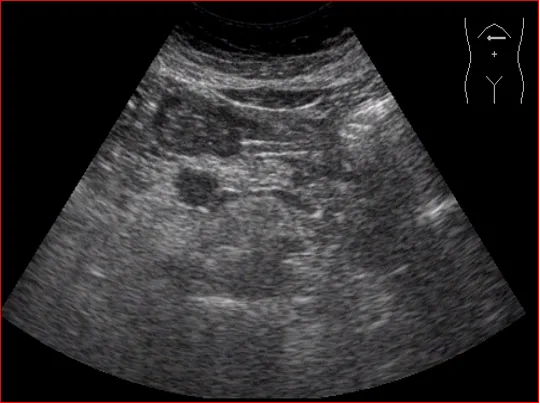

胰腺-长轴切面

胰体-纵切扫查